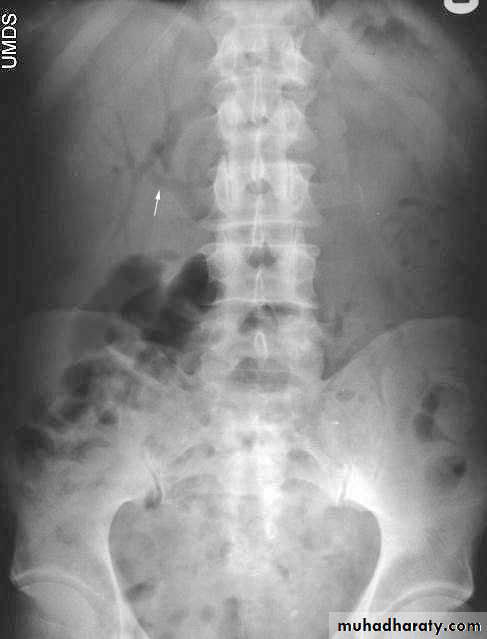

Abdominal calcifications

Assessment of the shape and pattern of abdominal calcification will usually limit the diagnosis to one or two choices. Calcification in the abdomen are likely to be :1. Pelvic vein phleboliths: very common, may be mistaken for urinary stones & fecoliths

2. Calcified mesenteric LN: caused by old TB. They are irregular, very dense and mobile

3. Vascular calcification: e.g. aortic aneurysm which best assessed on lateral film

11. Pancreatic calcification: occur in chronic pancreatitis & diagnosed from it's position

12. Faecoliths seen in colonic diverticulae or in the appendix. The presence of appendicolith is a strong indicator of acute appendicitis, often with perforation.

13. Renal stones and other calcifications of the urinary tract